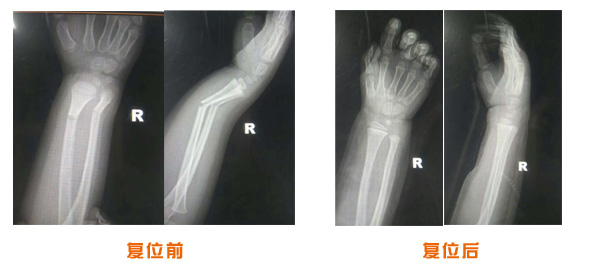

肥城市安駕莊梁氏骨科醫(yī)院是一所以梁氏手法正骨配合膏藥為特色的現(xiàn)代化專科醫(yī)院。

梁氏骨科術(shù)始創(chuàng)于清雍正年間,歷經(jīng)八代,至今已有三百年歷史。據(jù)1929年泰安縣志載“梁瑞圖先生,字增生,號(hào)蓮峰,安駕莊人,精岐黃并發(fā)明接骨,凡跌打車凡跌打車軋皮不破而碎骨者......【詳細(xì)】 |